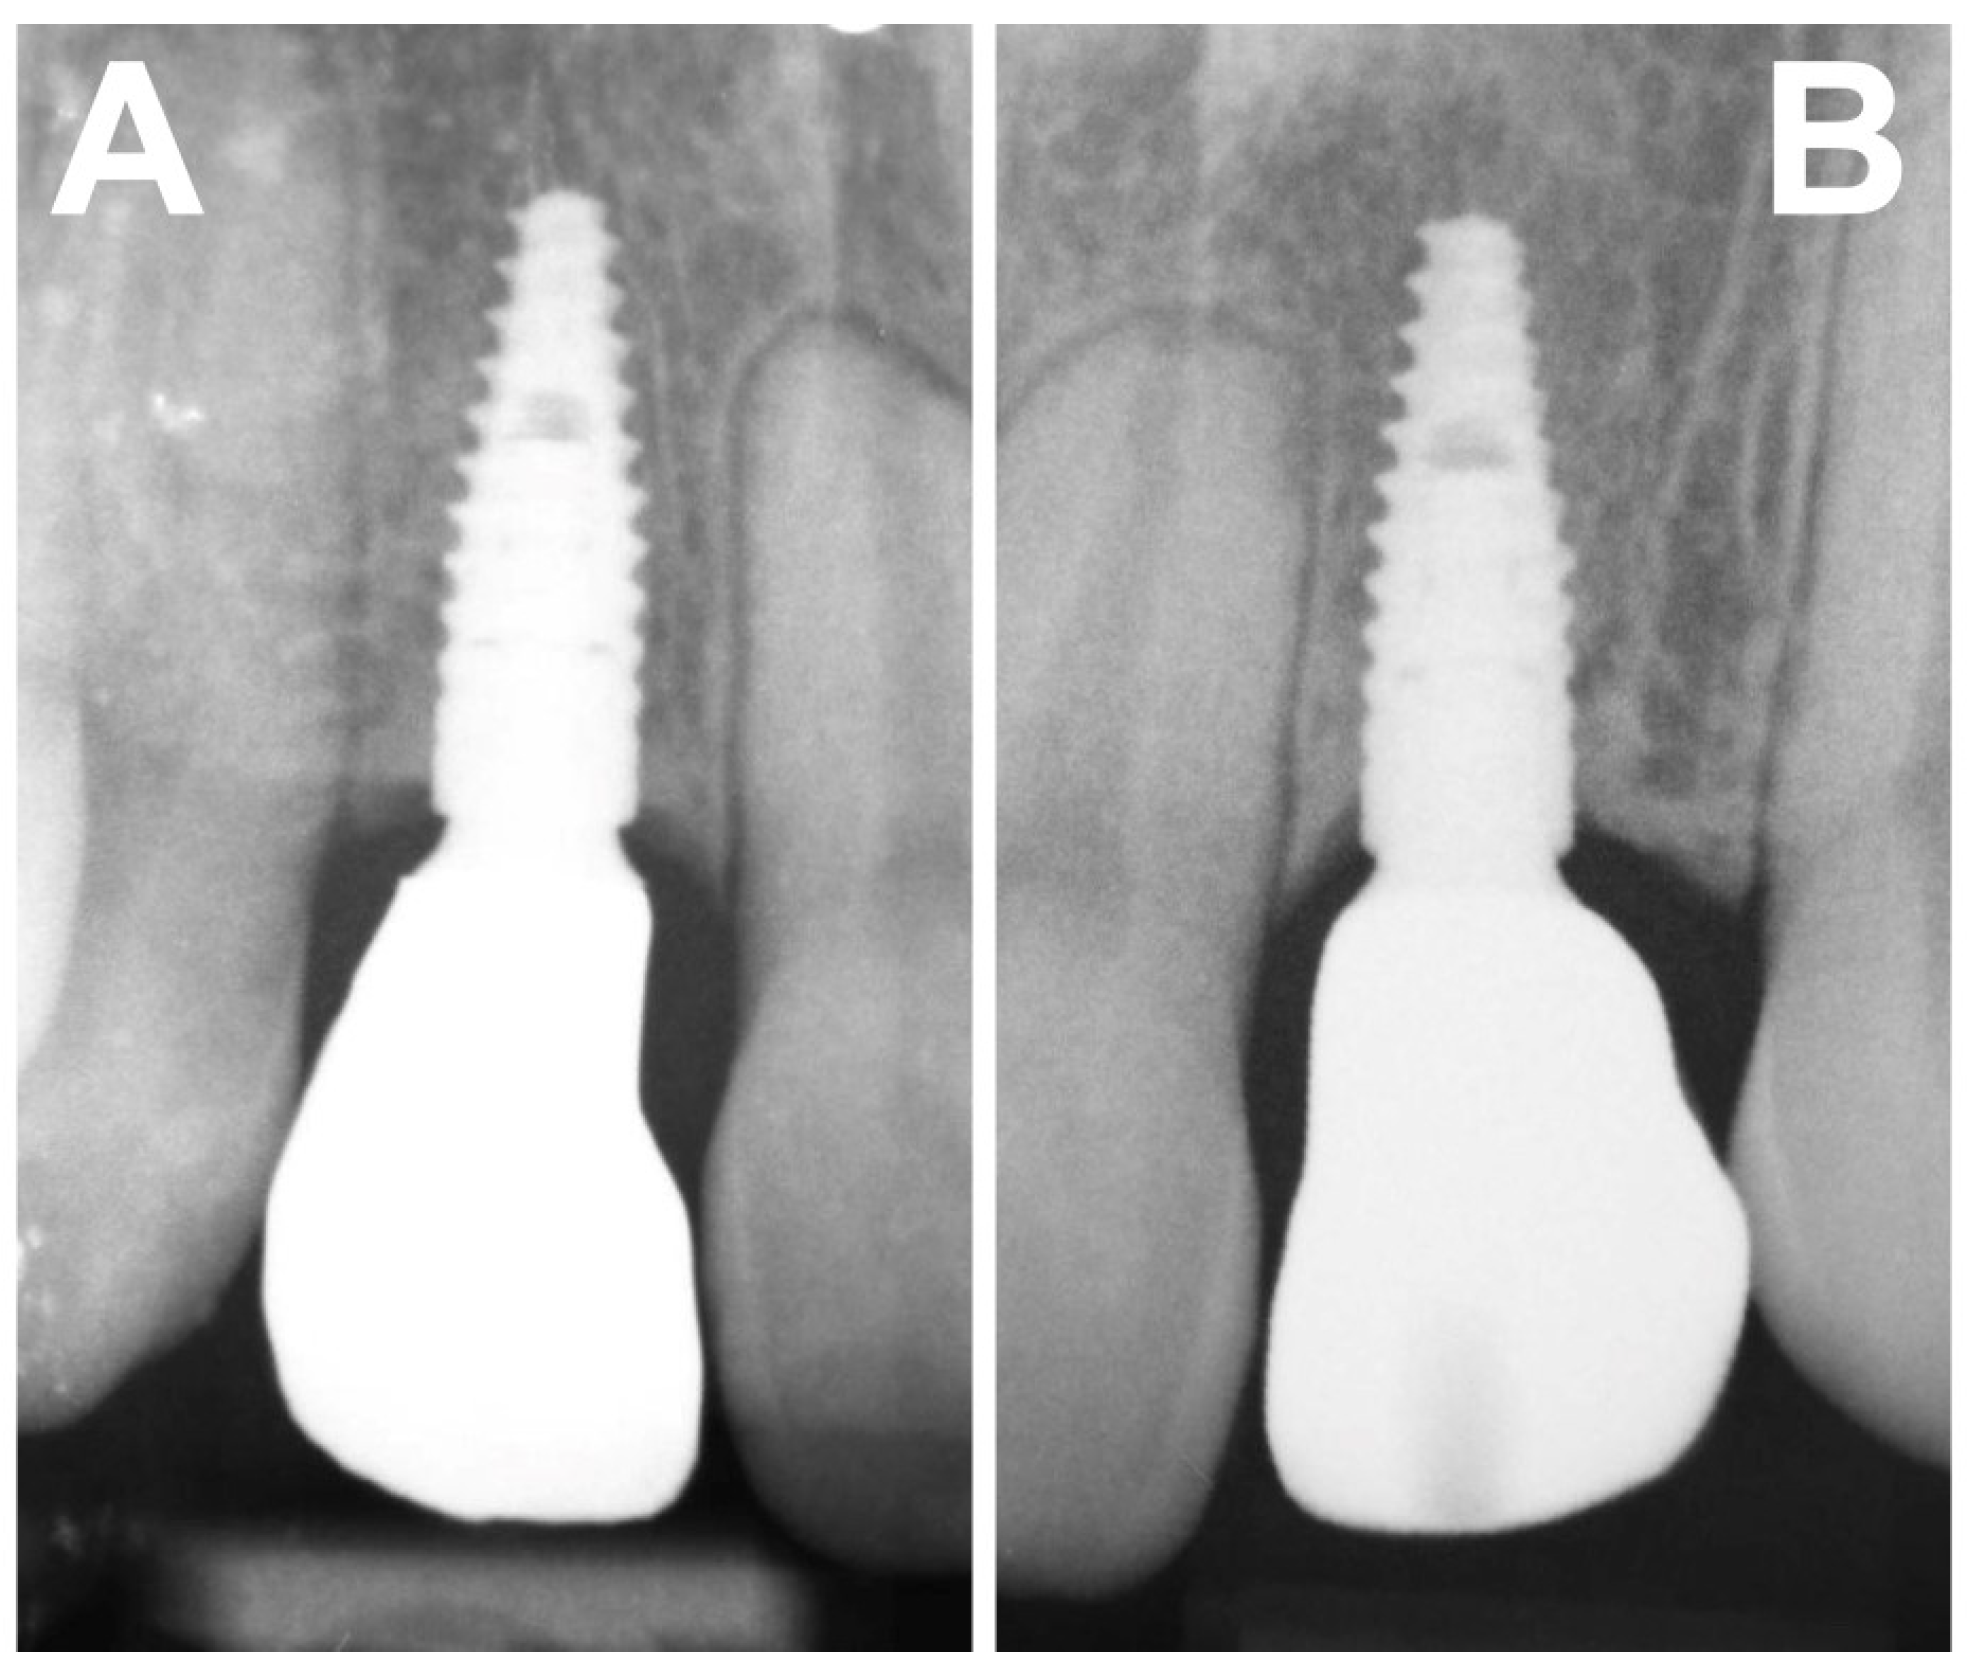

- marginal bone tissue (radiographic evaluation).

| Marginal bone tissue (RX) | Marginal resorption > 1.5 mm | Marginal resorption < 1.5 mm | No marginal resorption |